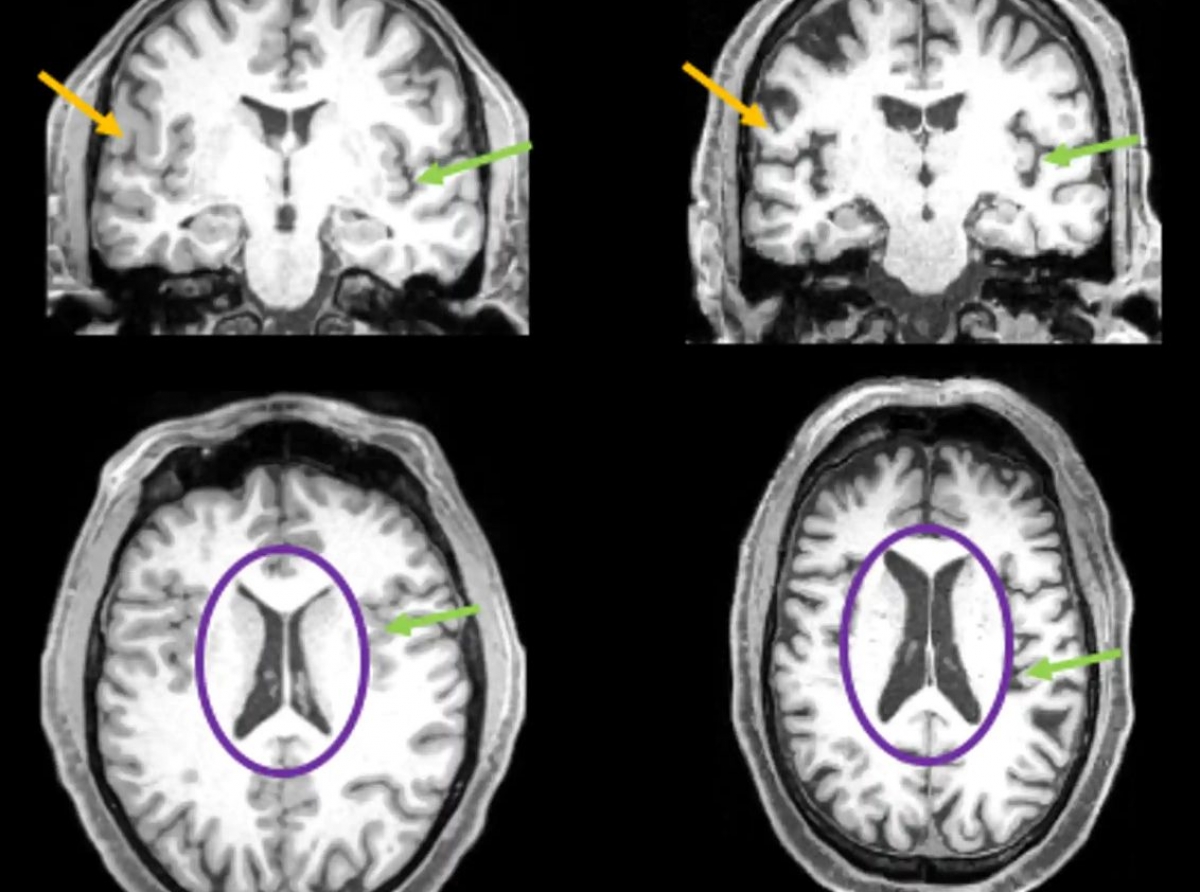

Neuroimágenes antes y después de covid

El equipo pronto se percató de diferencias profundas en la cantidad de materia gris entre las personas que sufrieron de covid y las que no. En especial, la densidad de materia gris en tejidos cerebrales de los lóbulos frontal y temporal fue más reducida en el grupo que tuvo covid. En el grueso de la población general, es normal observar algunos cambios en el volumen o grueso de la materia gris según el individuo envejece, pero los cambios en el caso de los sujetos que tuvieron covid fueron anormalmente mayores que el promedio. Cabe notar que, cuando los investigadores separaron al grupo de individuos que requirieron hospitalización for efecto del covid, los resultados fueron iguales que en aquellos que experimentaron un caso más leve. Es decir, las personas infectadas con covid presentaron una pérdida de volumen cerebral aun cuando la enfermedad no requirió de hospitalización.

¿Qué significan estos cambios en el volumen cerebral? Casi desde el inicio de la pandemia, uno de los síntomas más comúnmente reportados fue el de la pérdida de los sentidos del gusto y el olfato. Curiosamente, todas las regiones afectadas del cerebro que los autores de este estudio vieron en sujetos recuperados de covid están ligados al bulbo olfatorio, una estructura cercana a la región frontal del cerebro que transfiere señales olfativas desde la nariz a otras regiones del cerebro. El bulbo olfatorio tiene conexiones con regiones del lóbulo temporal; comúnmente nos referimos al lóbulo temporal en el contexto del envejecimiento y la enfermedad de Alzheimer porque ahí se ubica el hipocampo, que tiene un rol clave en el proceso de envejecer dada su función en procesos cognitivos y de la memoria.